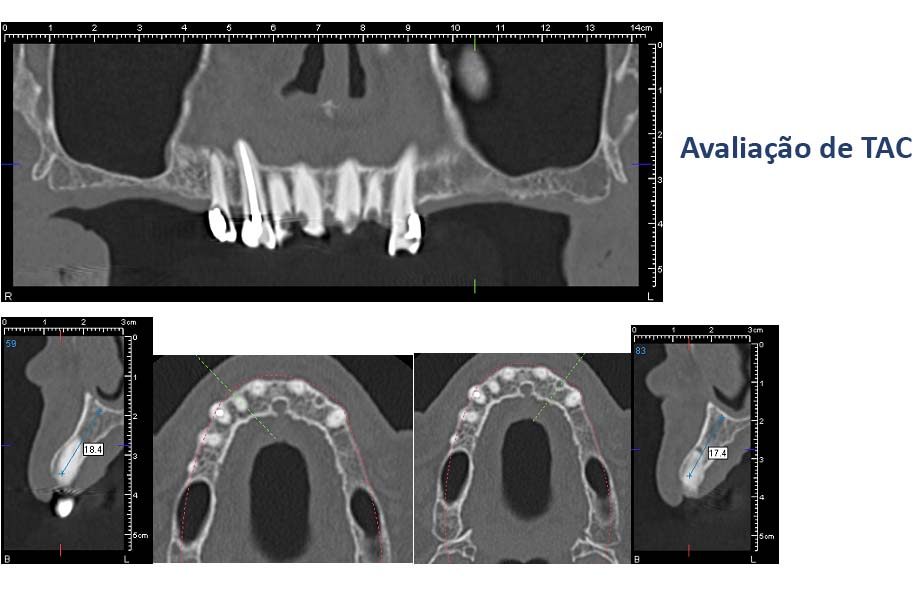

2. Radiografias

5. Pedido de exames ( TACs ) complementares se necessário.